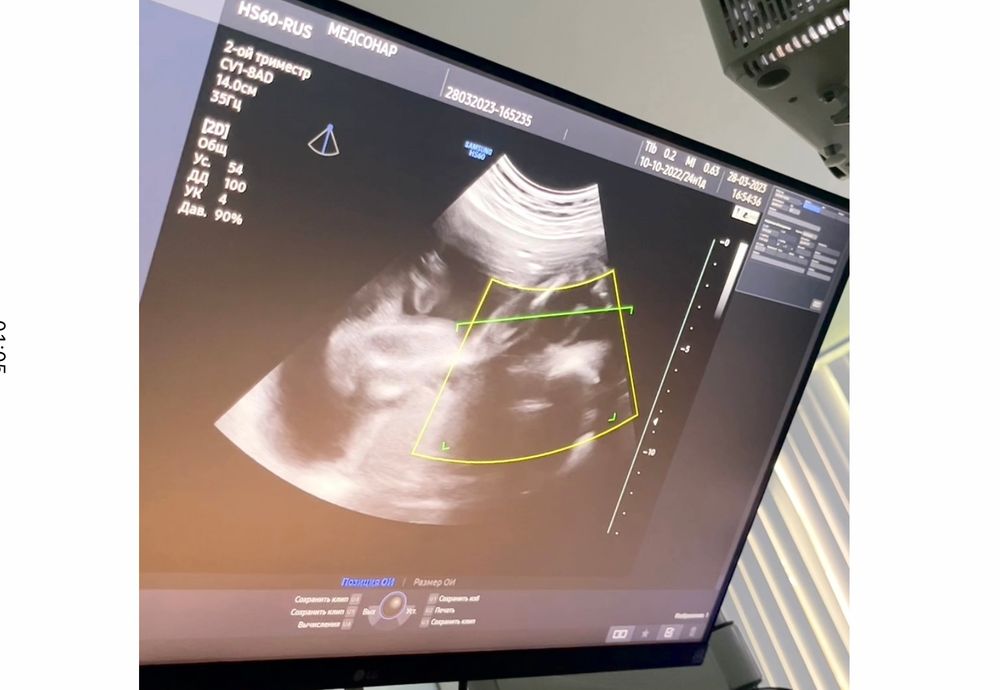

Мальчик или девочка,как думаете?☺️Узи 20недель,врач говорит что больше похоже на девочку.

Пол малыша

Катя, прячется ребенок,вот пытаюсь по фото сама догадываться до 3 скрининга😅

Наташа, не похоже на ногу , больше на пуповину либо перчик )))